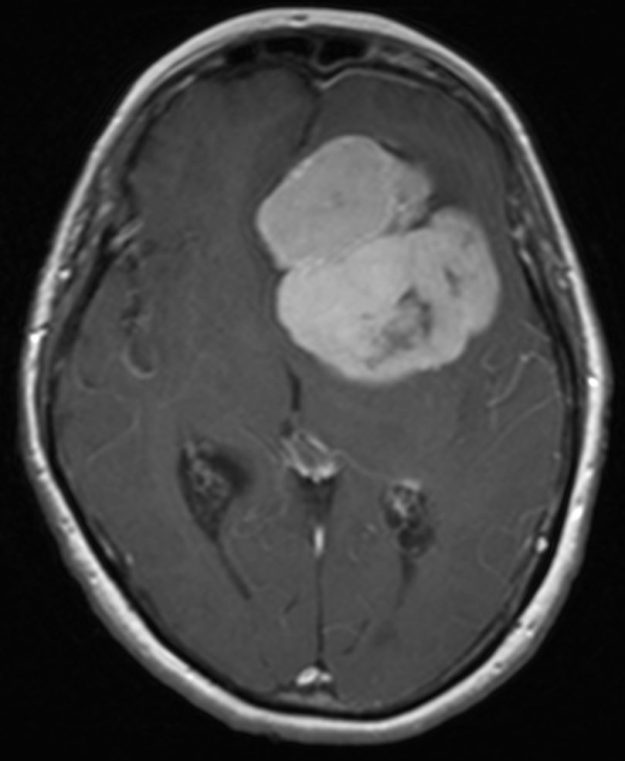

Μηνιγγίωμα περιοχής Επίφυσης

Ασθενής γυναίκα, 52 ετών η οποία παρουσίασε υπακουσία και επεισόδια πάρεσης του προσώπου. Ο απεικονιστικός έλεγχος με μαγνητική τομογραφία ανέδειξε ευμεγέθη όγκο στην περιοχή της επίφυσης (κωνάριο) με πίεση επί του μεσολοβίου, του τετραδύμου πετάλου και λοιπών εν’ τω βάθει δομών. Διενεργήθη δεξιά ινιακή, διασκηνιδιακή, διαδρεπανική προσπέλαση και ολική αφαίρεση της βλάβης. Η μετεγχειρητική αξονική…